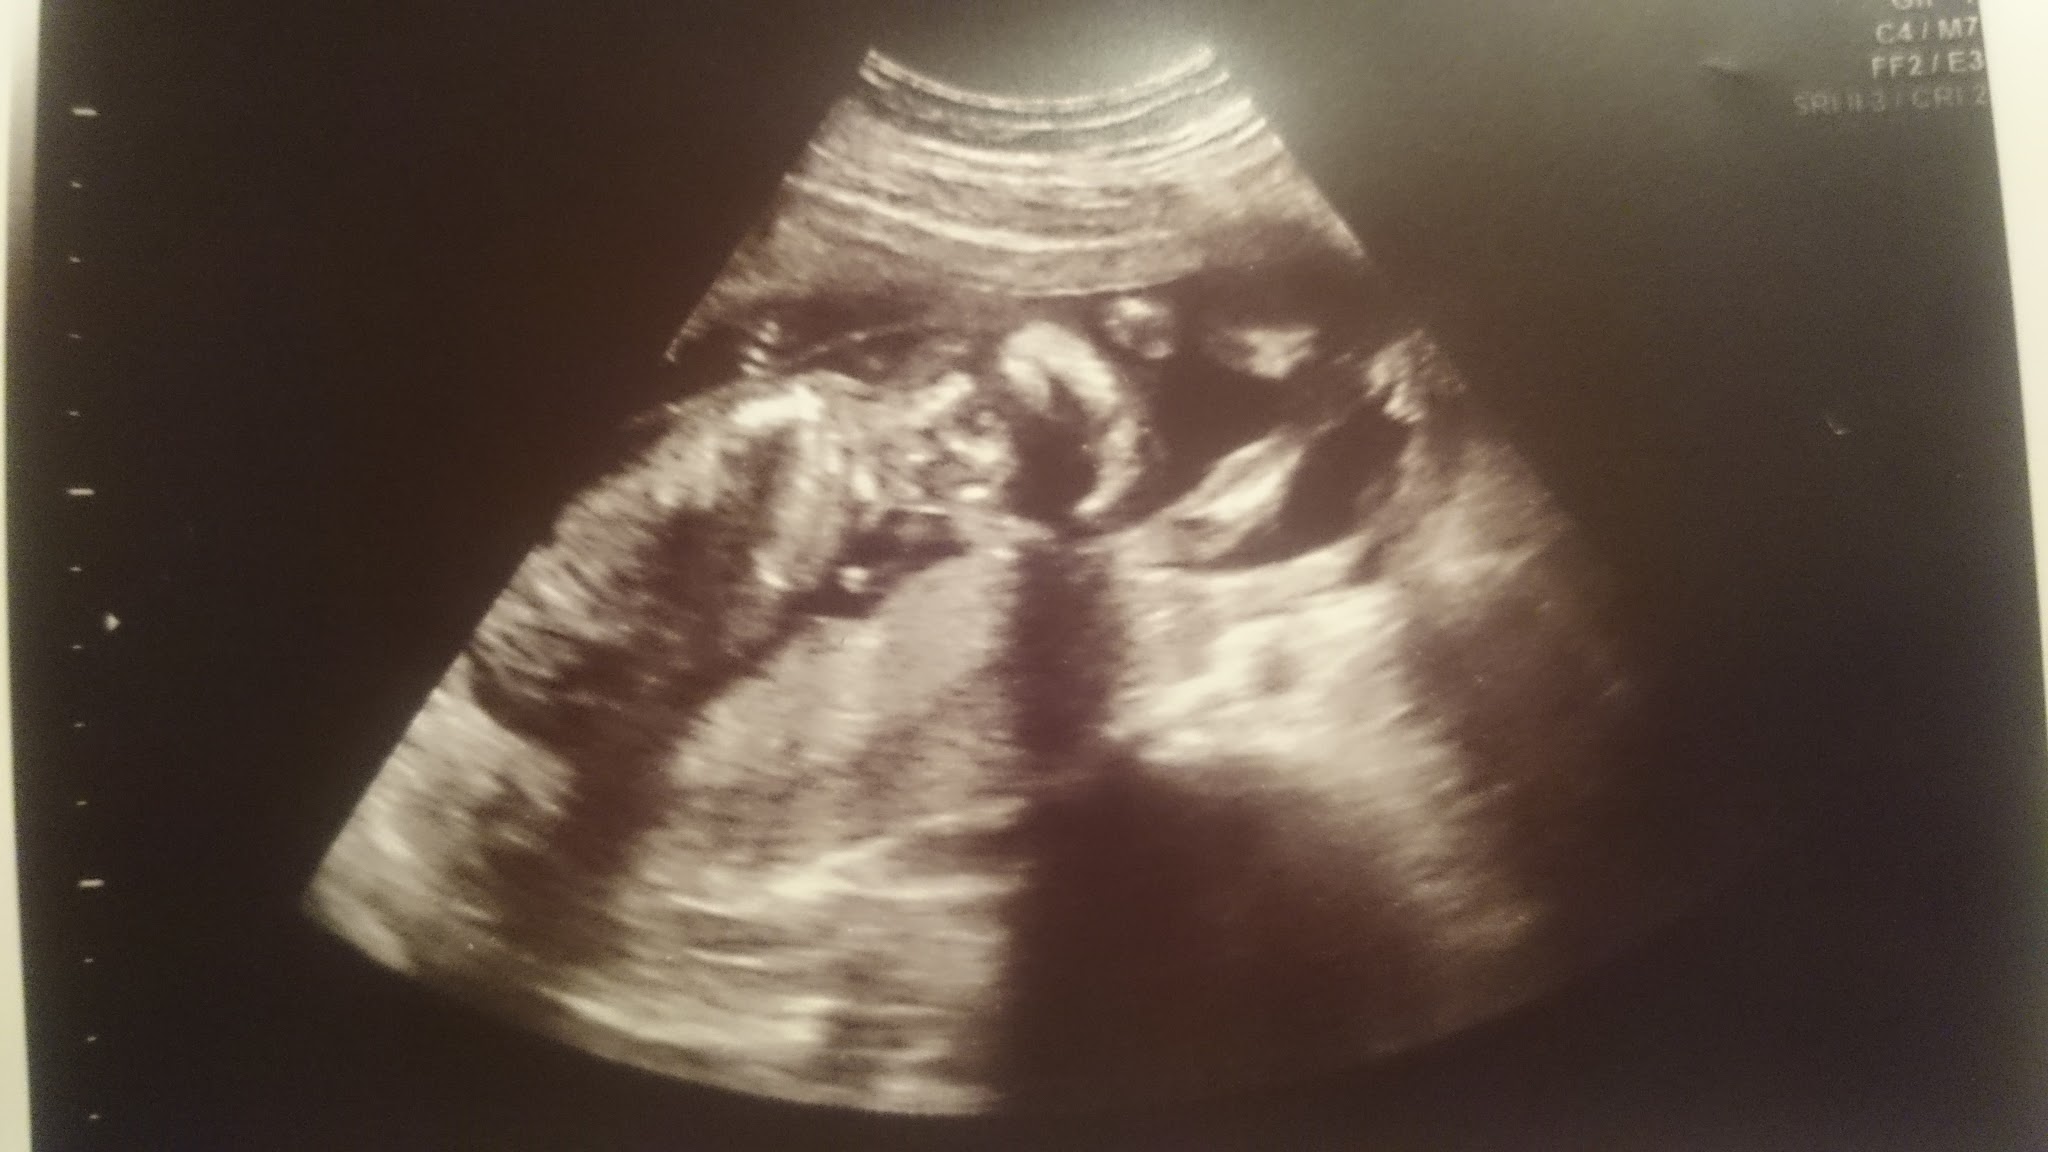

Slicznosci[emoji3]U mnie też ostatnio jakoś depresyjnie. Trochę słońca by się przydało. Ale USG zawsze poprawia nastrójOto moje szkraby. Jeden niestety się chowa.

Zobacz załącznik 836008 Zobacz załącznik 836007